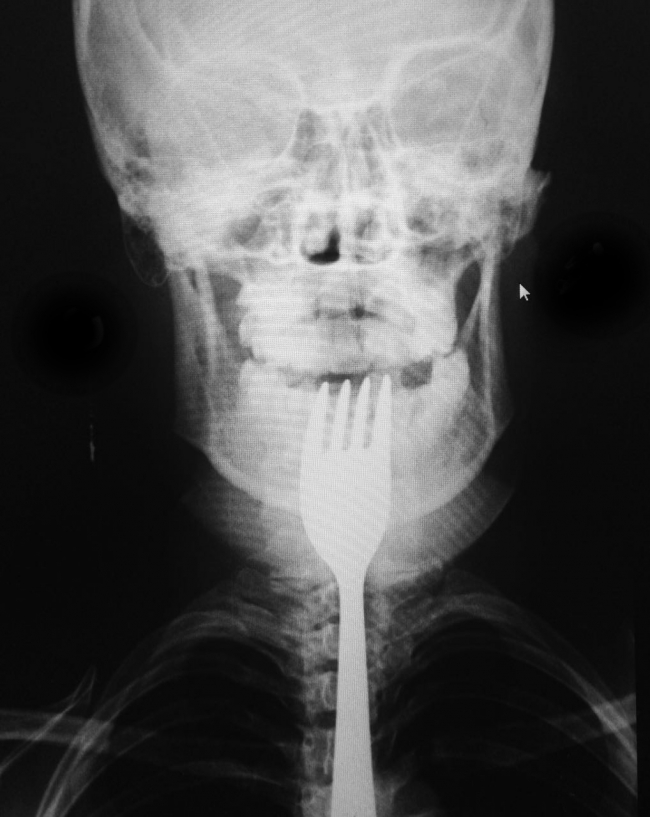

Bursa'nın Orhangazi ilçesinde dişini karıştırdığı çatal boğazına girip takılan genç kız, hastaneye kaldırıldı.

Alınan bilgiye göre, Üreğil Mahallesi'nde ailesiyle yaşayan 19 yaşındaki N.A, çatalın ters bölümüyle dişini karıştırmaya başladı. Bu sırada genç kızın boğazına çatal girdi.

Taksici babası İ.H.A. tarafından Orhangazi Devlet Hastanesine kaldırılan N.A, ilk müdahalenin ardından Uludağ Üniversitesi Tıp Fakültesi Hastanesine sevk edildi.

Burada yapılan müdahale sonucu genç kızın boğazına takılan çatal çıkarıldı.